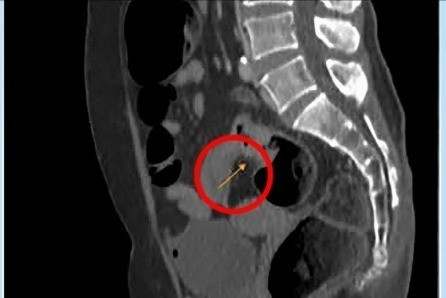

Chụp MRI cho thấy khối u ở trực tràng (mũi tên vàng) của bệnh nhân. Ảnh BVCC

Tại bệnh viện, kết quả nội soi trực tràng của bệnh nhân cho thấy u ở lòng trực tràng phát triển gây bán tắc, dạng vòng nhẫn, thâm nhiễm cứng. Kết quả MRI 3 tesla ghi nhận thành ruột dày không đều tại chỗ nối trực tràng với đại tràng sigma (12 mm), trên 30 mm không rõ cấu trúc, tổn thương dạng không nhầy chiếm hết chu vi, gây hẹp lòng đại tràng tại vị trí này.